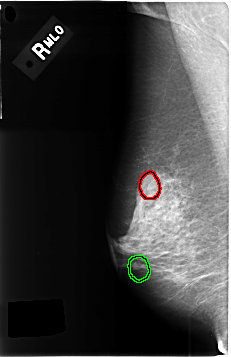

C_0458_1.RIGHT_MLO

FILE: C_0458_1.RIGHT_MLO.OVERLAY

TOTAL_ABNORMALITIES 2

ABNORMALITY 1

LESION_TYPE CALCIFICATION TYPE AMORPHOUS DISTRIBUTION CLUSTERED

ASSESSMENT 4

SUBTLETY 3

PATHOLOGY MALIGNANT

TOTAL_OUTLINES 1

BOUNDARY

ABNORMALITY 2

PATHOLOGY BENIGN